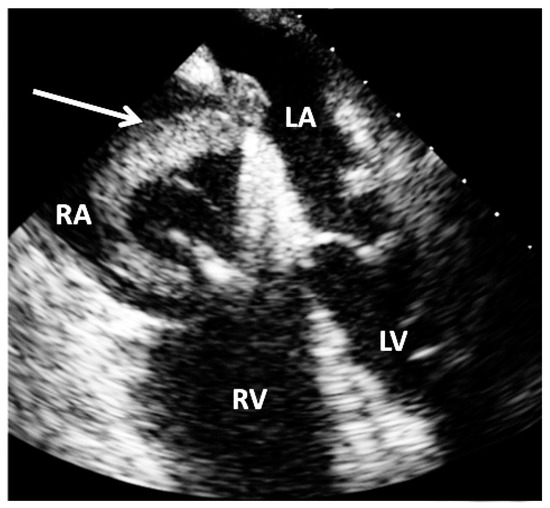

Two venous retrograde approaches (6 and 8 F sheaths) were inserted in the common femoral vein. Using a 8 F Multipurpose guiding catheter and a 6 F long diagnostic Judkins right catheter (i.e., telescoping technique), a soft tip guide wire was gently advanced firstly in the right atrium, then in the right ventricle and finally in the right pulmonary artery. At that moment, a selective pulmonary angiography confirmed the presence of a massive PE and while preparing the AngioJet™ catheter, a temporary pacemaker was positioned in the right ventricle. Finally, the Angiojet system was advanced through the 8 Fr guiding catheter and activated (max. 20 s) inside the pulmonary occlusion. During the thrombectomy procedure, the TEE confirmed the presence of a large serpentine thrombus in the right atrium floating through the PFO into the left atrium (Figure 2).

Figure 2. Trans-oesophageal four-chamber view echocardiography showing a large impending paradoxical embolism (white arrow) extending from the right atrium (RA) to the left atrium (LA) via a patent foramen ovale. RV = right ventricle; LV = left ventricle; LA = left atrium; RA = right atrium.